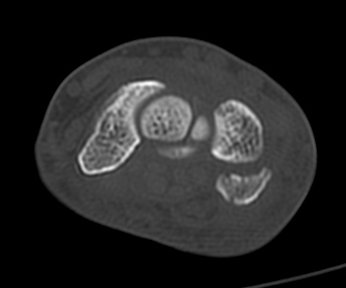

ÄÄÇ»ÅÍ ÃÔ¿µ :  Äá¾Ë»À ºÐ¼â°ñÀýÀÌ °üÂûµÊ(»çÁø 7, 8, 9, 10).